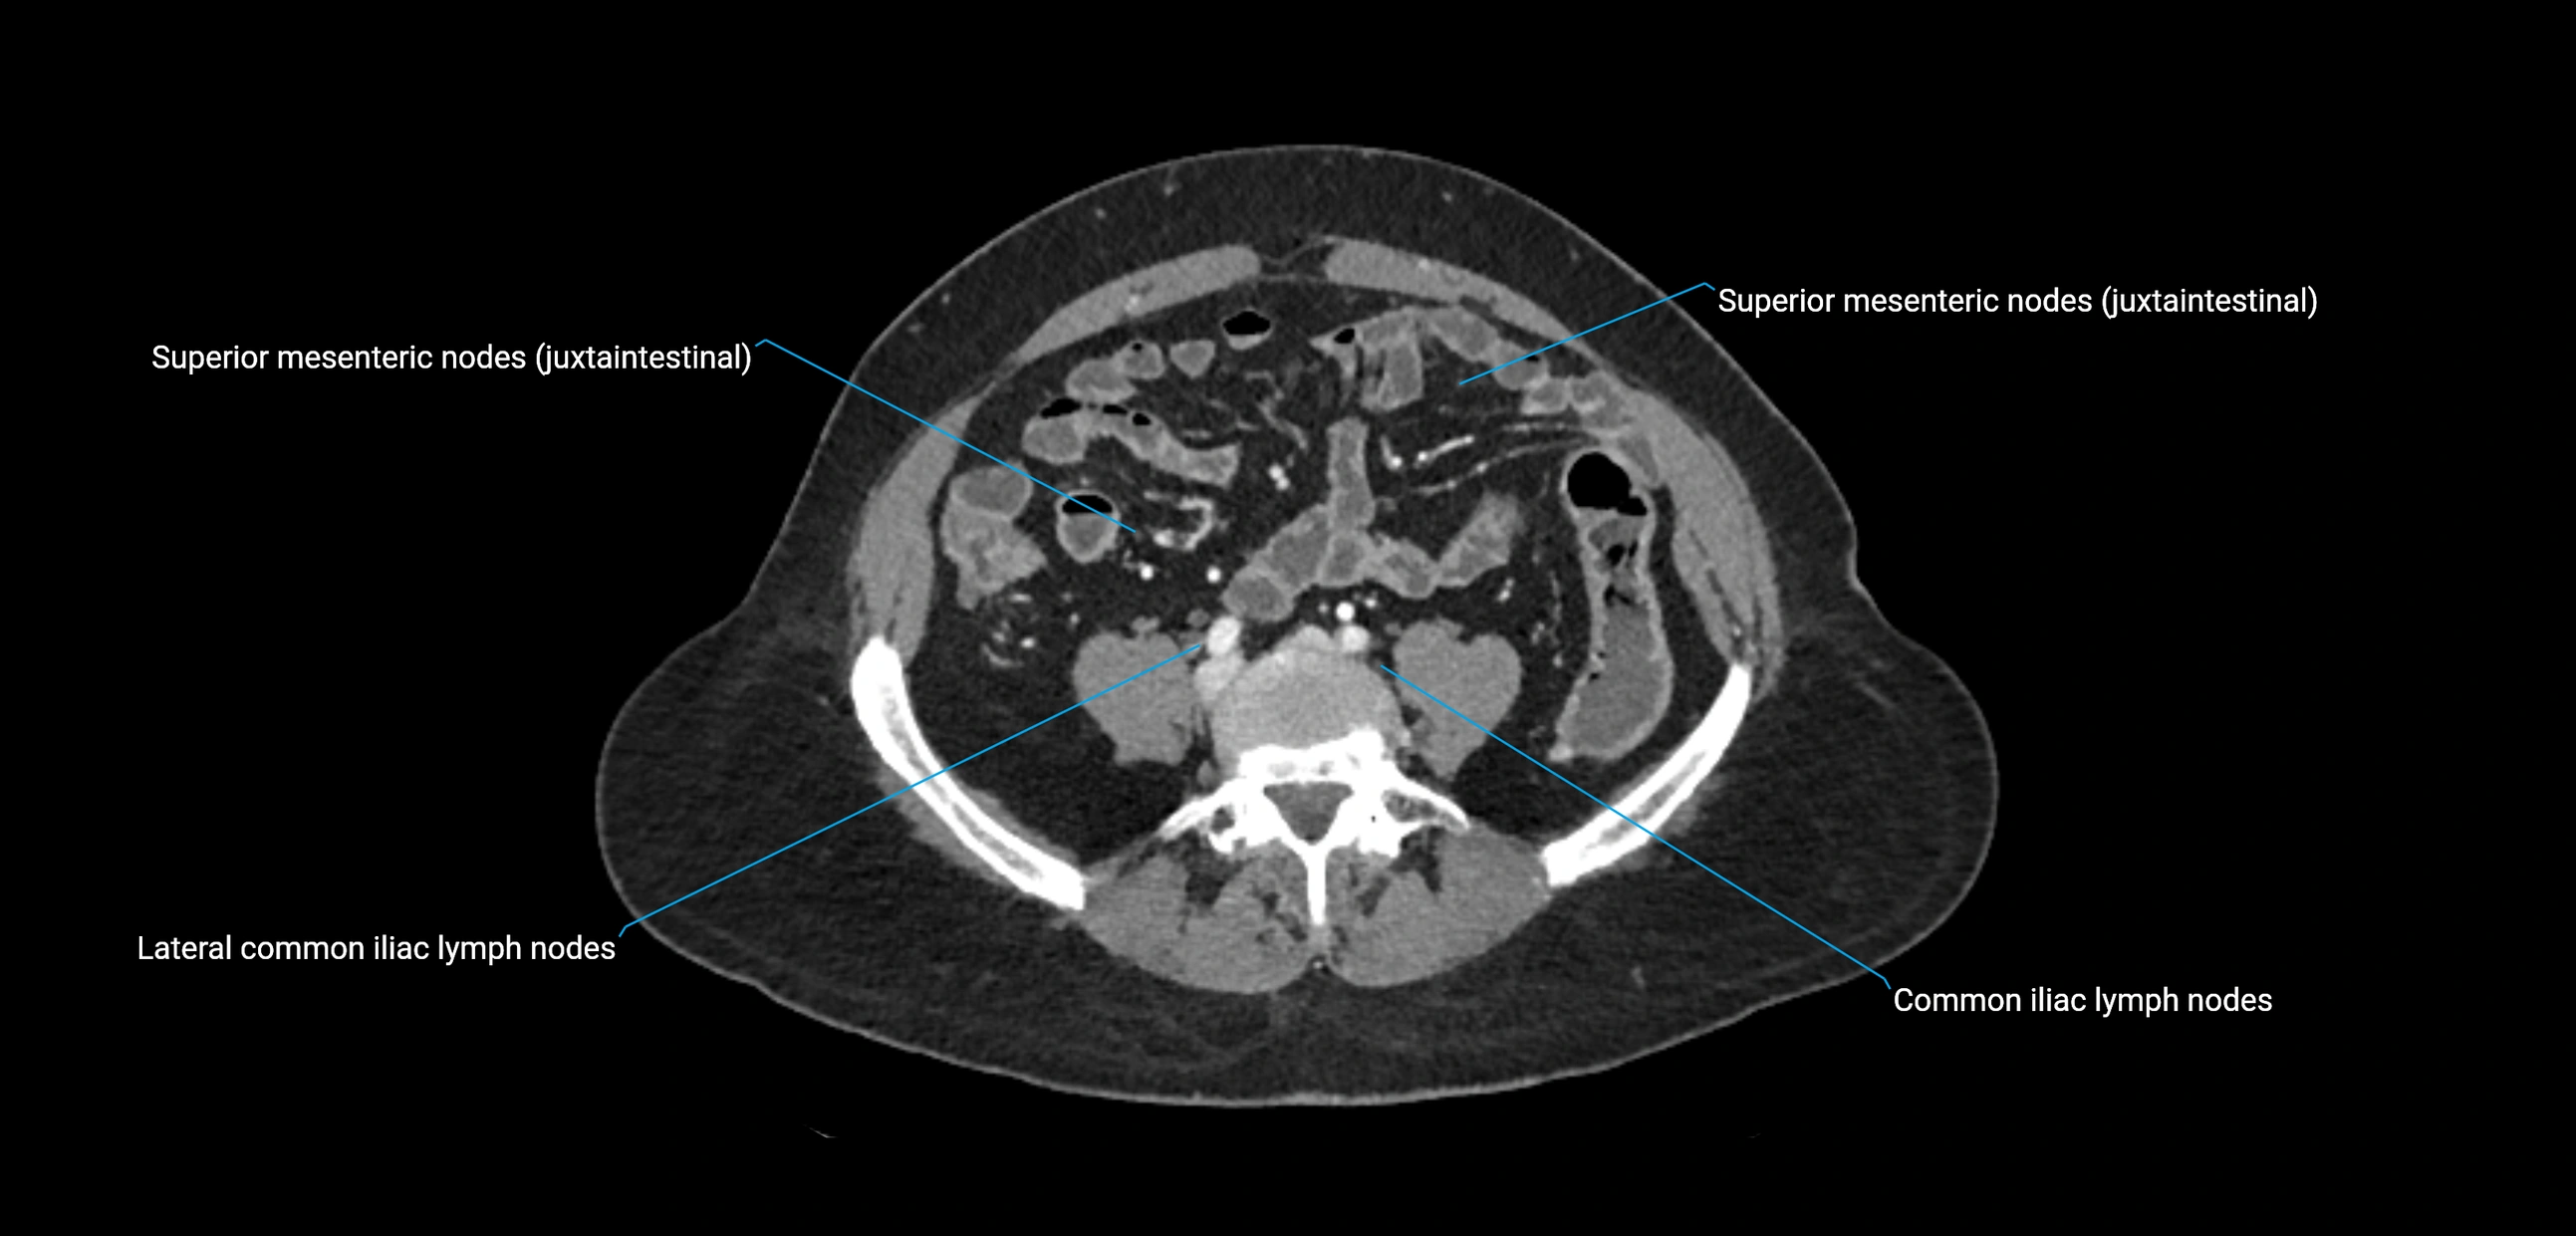

CT Appearance

CT Pre-Contrast:

• Nodes appear as soft-tissue density nodules adjacent to the aorta and IVC

• Calcification may be seen in chronic infections (e.g., tuberculosis)

CT Post-Contrast:

• Normal nodes enhance homogeneously

• Malignant nodes may show heterogeneous enhancement, central necrosis, or conglomerate formation

• Size >1 cm short axis is suspicious, though morphology and distribution are equally important